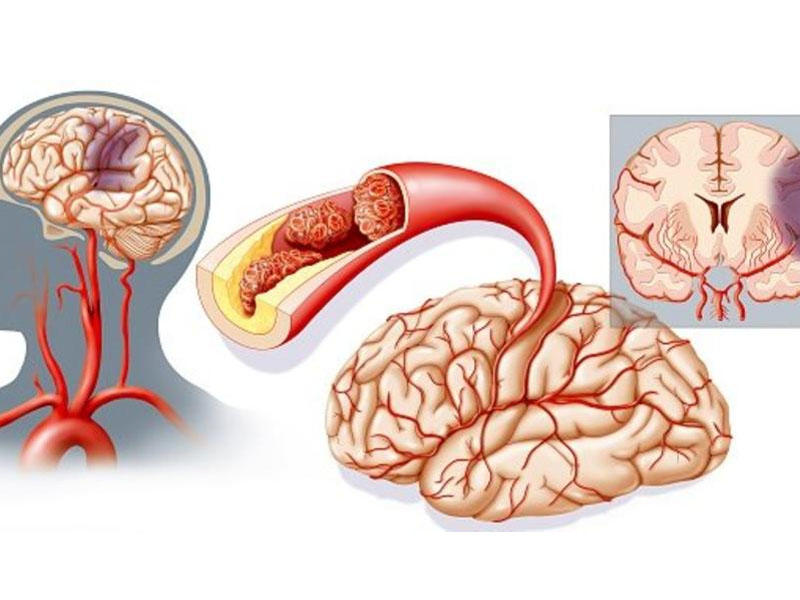

Ишемический инсульт левой стороны: симптомы и реабилитация